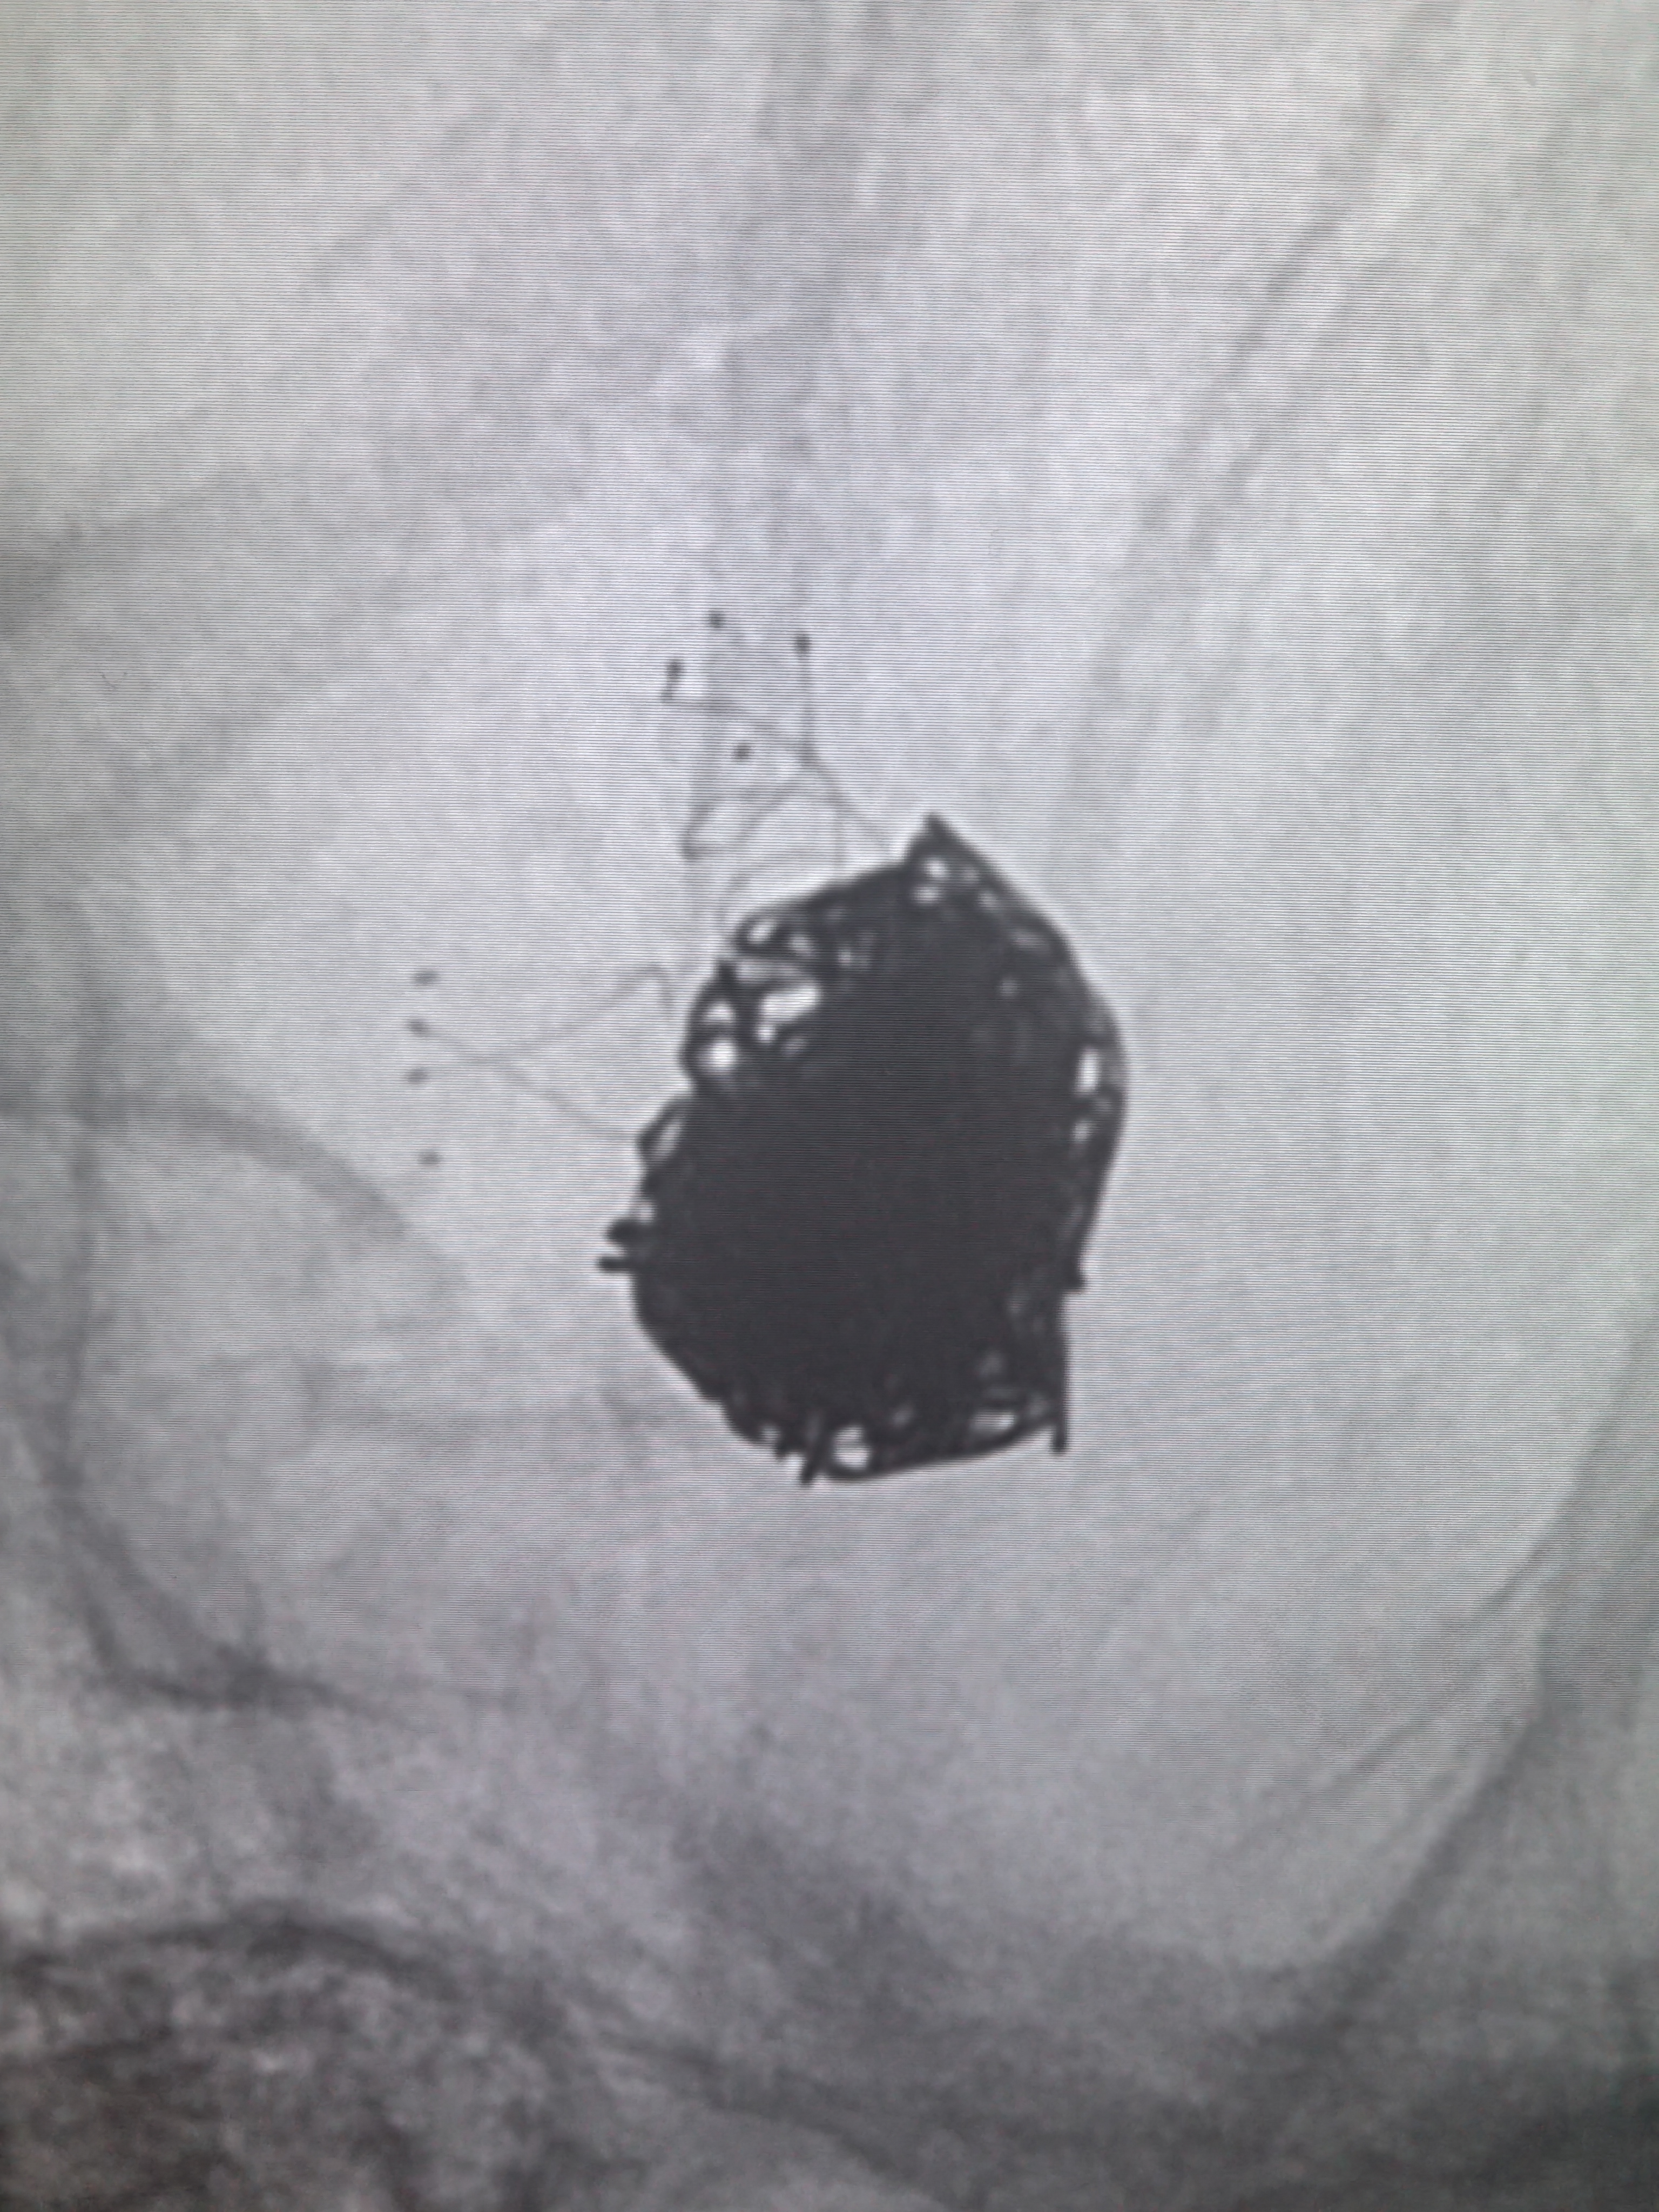

蒙片看支架及弹簧圈!支架打开良好!

动脉瘤栓塞满意,胚胎型大脑后动脉还有血流通过,栓塞致密程度还不够,考虑破裂动脉瘤,先降低出血风险,动脉瘤大,大小约12.6*8.5mm,复发风险高,将来复发再考虑血流导向植入!